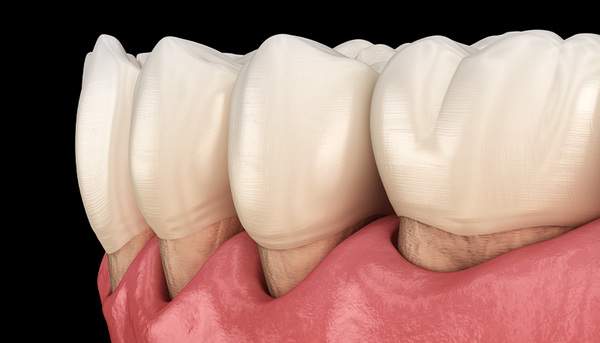

妊娠性歯肉炎

妊婦さんになると小さな命を守るために身体に様々な変化が起こります。それはお身体だけでなくお口の中にも影響を与えます。

妊娠してから歯ブラシの時に歯茎から出血するようになった、歯茎が腫れぼったいと感じている方は妊娠性歯肉炎かもしれません。

原因

妊娠すると歯肉炎にかかりやすくなってしまうのは女性ホルモン(エストロゲン)が体内で増え、それを好むある種の歯周病菌が増殖していくためです。

また、妊娠中はつわりなどでしっかり歯ブラシが行えないうえ、唾液が酸性化し口が乾燥しやすくなります。また、唾液の粘性が増すためお口の中の汚れが溜まりやすくなります。

そして、妊娠中は妊娠前に比べ食事の回数や内容が不規則になり細菌の活動も活発になります。

歯周病が悪化する一因となるエストロゲンは妊娠中期〜後期にかけて増えるためこの時期に妊娠性歯肉炎を発症する方が多いです。

ただ、しっかりと歯ブラシをしてプラークコントロールを行えば、歯肉の炎症はおさえられるので、お家でのセルフケアに合わせて歯科医院でのプロフェッショナルケアもおすすめしています。